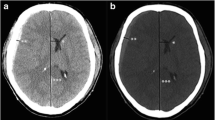

Inter-rater reliability of the two radiologists is presented in Table 2. The kappa value (k = 0.80–0.87) indicates substantial to almost perfect inter-rater reliability. The HU values of the injury or non-injury site are indicated in Figs. 2 and 3. Only the HU value of WM in the injury site of the death group was decreased significantly. There was no significant difference in the DDM between the survival group and death group (p = 0.25) (Fig. 4). We also reanalyzed the DDM-derived hematoma thickness. The hematoma thickness was 5.2 ± 1.2 mm in the death group and 3.8 ± 2.0 mm in the survival group. There was no significant difference in the DDM subtracted hematoma thickness between the survival group and death group (p = 0.45). However, the DDM in the death group was slightly higher than that in the survival group. The DDM did not correlate with the initial FDP, SBP, or GCS. ROC analysis for HU of WM of the injury site is shown in Fig. 5. A cut-off value of 31.5 for HU of WM showed 80.0 % sensitivity and 99.9 % specificity for death; the AUC was 0.91. Of the 24 surviving patients, however, only two had a HU value of less than 31.5.

HU values measured at the initial CT were found to be the best predictor of outcome in patients with subdural hematoma due to brain edema. To the best of our knowledge, this is the first study to assess brain edema due to head trauma with subdural hematoma using head CT measurement expressed in HU of GM or WM. Especially, a cut-off value of 31.5 HU showed sufficient accuracy in discriminating between patients who survived and those who died. The HU values in the whole WM of patients with severe micro-angiopathic disease, demyelination or leukodystrophy/encephalopathy are decreased. In the immediate period after an injury such as acute subdural hematoma, there is a difference in the HU level of the WM between the injured side and non-injured side. In this study, the HU level of the non-injured side was 37.6 in the death group and 39.2 in the survival group. This finding is different between an injury and the above diseases.

Interestingly, traumatic brain injury caused an increase in the water content of the WM. WM edema has been observed and previously reported in relation to several diseases [16]. In post-cardiac arrest patients with brain edema, the HU values of WM showed no relative change in the hypoxic group, but the HU values decreased in the GM [17–20]. Changes in HU values depend on the water content of the brain tissue. There is more water content in the GM than in the WM following a hypoxic insult to the brain that results in edema, and such edema is more often present in the cerebral cortex than in the WM [16]. In brain cell death, the fatty myelin does not change during the acute phase; however, the intra- and extracellular water content does change after cell death. The results of the present study are controversial in terms of the changes caused by traumatic brain injury. Our finding that HU values on head CT scans decreased in the WM at the injury site within a very short time following traumatic insult was interesting. The midline shift was greater than the thickness of the hematoma, meaning that the brain swelling was related to brain damage. Bartels reported that in patients with a traumatic acute subdural hematoma a clear correlation between midline shift and thickness of the hematoma was found [21]. All patients with midline shift exceeding the thickness of the hematoma by 3 mm or more died. This report supported our results of the brain swelling was related to brain damage.